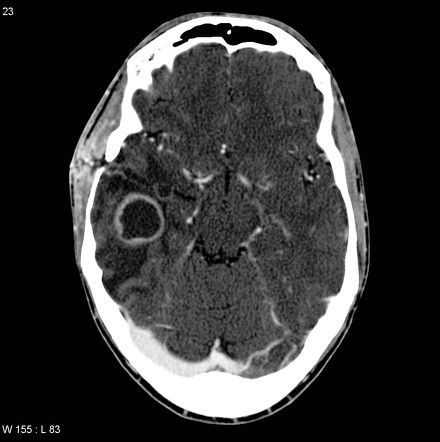

Brain abscess is a focal suppurative infection of the brain parenchyma commonly caused by streptococci but can be polymicrobial as well. It most commonly affects the frontal lobe, followed by the parietal lobe. Patients commonly present with headache, which is dull and constant in character, focal neurologic deficits, seizures, signs of raised intracranial pressure, and oculomotor and abducens nerve palsy. CT scan is the best initial test for the diagnosis, which shows a ring-enhancing lesion with a low-density core. Treatment is done by intravenous broad-spectrum antibiotics for at least 6-8 weeks.